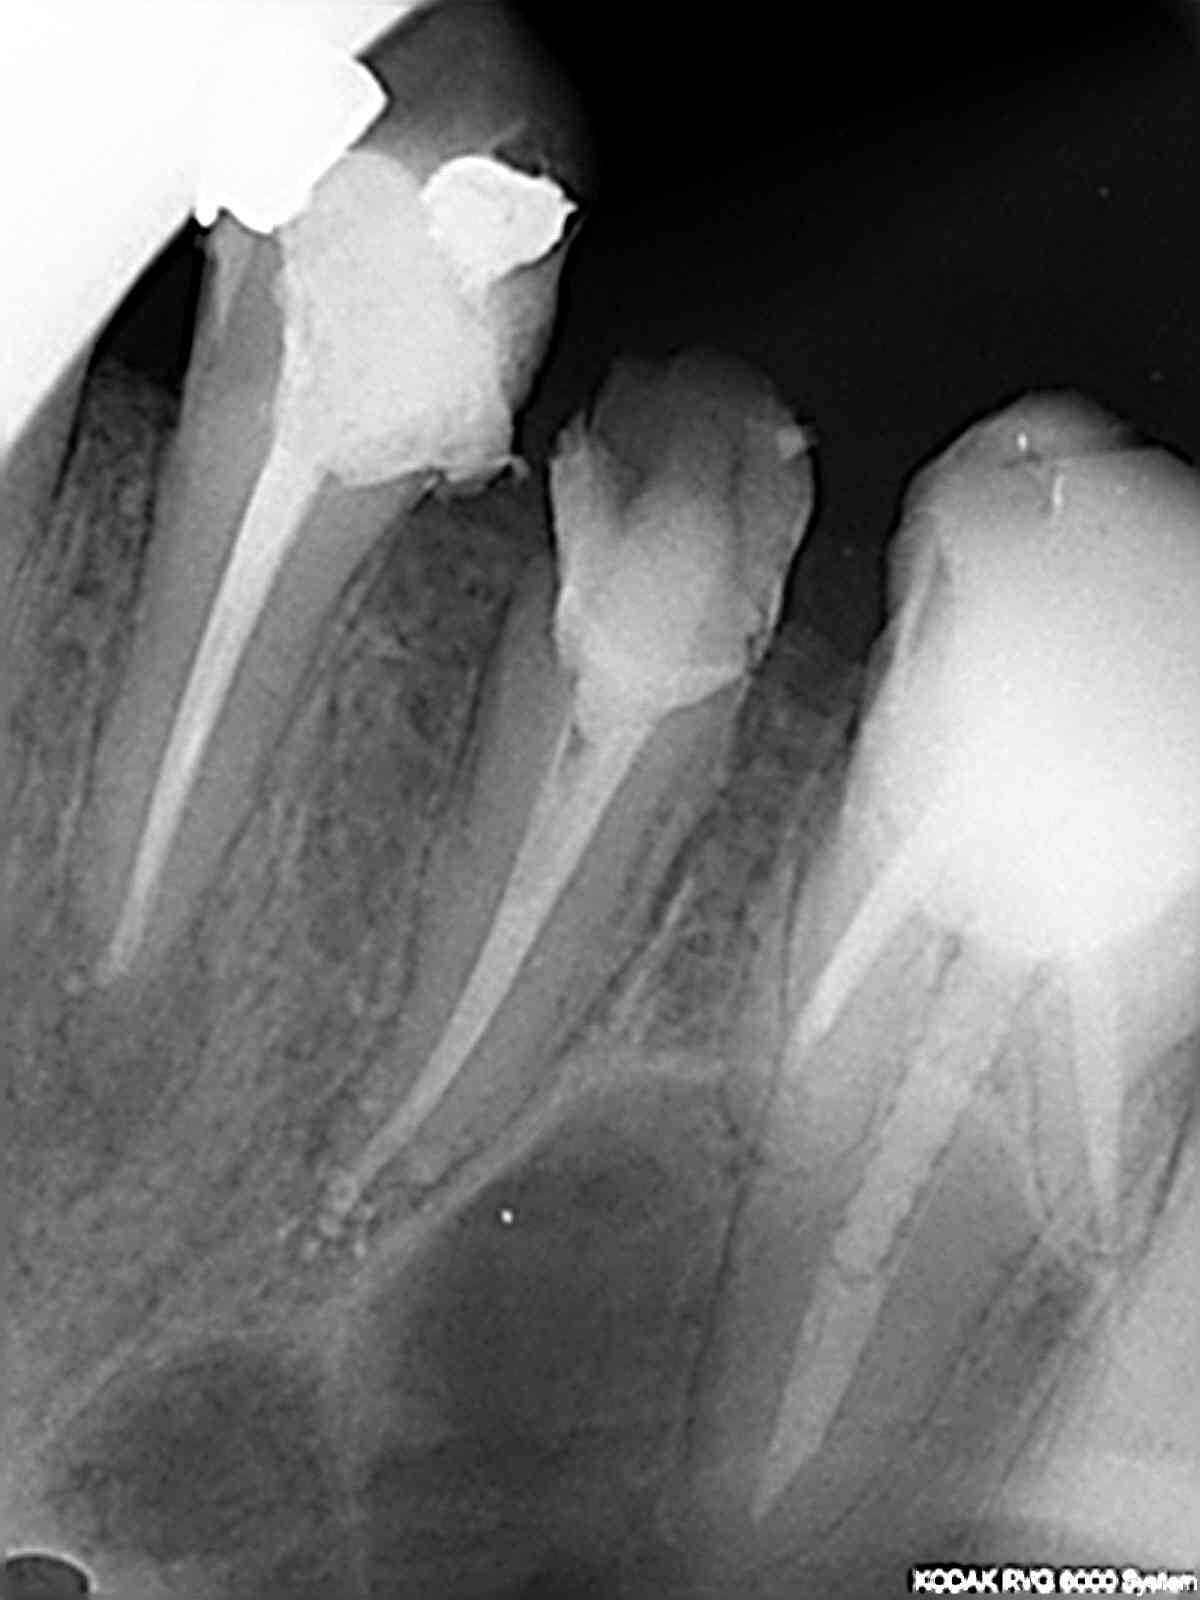

Sur la 14, c'est un Mc Spadden cassé dans la gutta: ça c'est assez fréquent mais pas très génant: instrument stérile noyé dans la gutta.